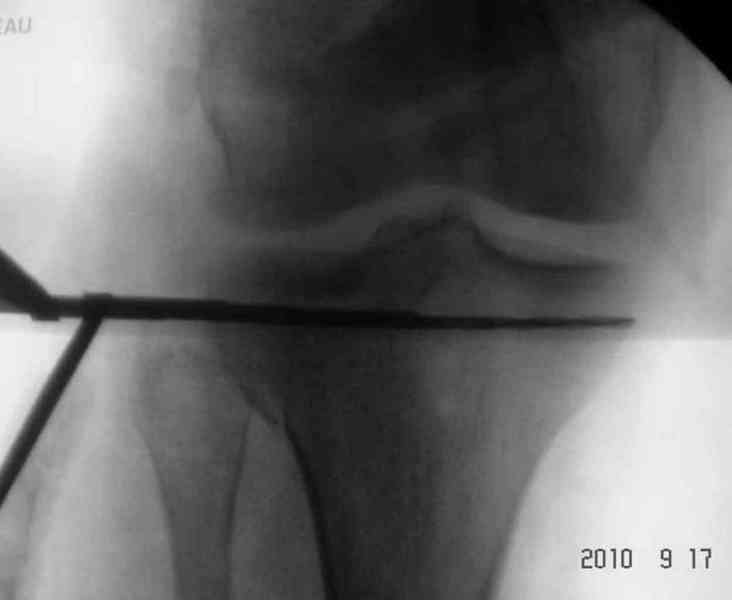

Вчера выполнена закрытая репозиця малоберцовой кости, промежуточный отломок расклинен с дистальным метаепифизом, выведен ближе к оси центрального отломка, вилка голеностопного сустава стала нормальной конфигурации, уменьшен вес вытяжения. Снимки представлю завтра.

Снимки до и после закрытой репозиции

Как всегда прекрасная презентация. Совершенно согласен с необходимостью сохранять мениск и вообще согласен со всем, кроме одного. Фиксация должна проводиться после правильно выполненной репозиции. Главная цель репозиции - это восстановить высоту наружного мыщелка. В норме наружный мыщелок выше внутреннего на 4-5 мм на снимке в переднее заднем направлении АР.

Необходимость репозиции возникает при снижении высоты от 3 до 5 мм по разным источникам. По моему опыту 4 мм. Если не восстановить высоту мыщелка возникает вальгизация коленного сустава с относительным расслаблением передней крестообразной связки. При этом развивается нестабильность коленного сустава из-за недостаточности ПКС.

На представленном после операционном снимке нет репозиции, на что указывает низкое положение тибиального плато и перекрытие кортикальных пластинок в метафизарной части - указано стрелкой. Обычно чрескожную фиксацию я применяю